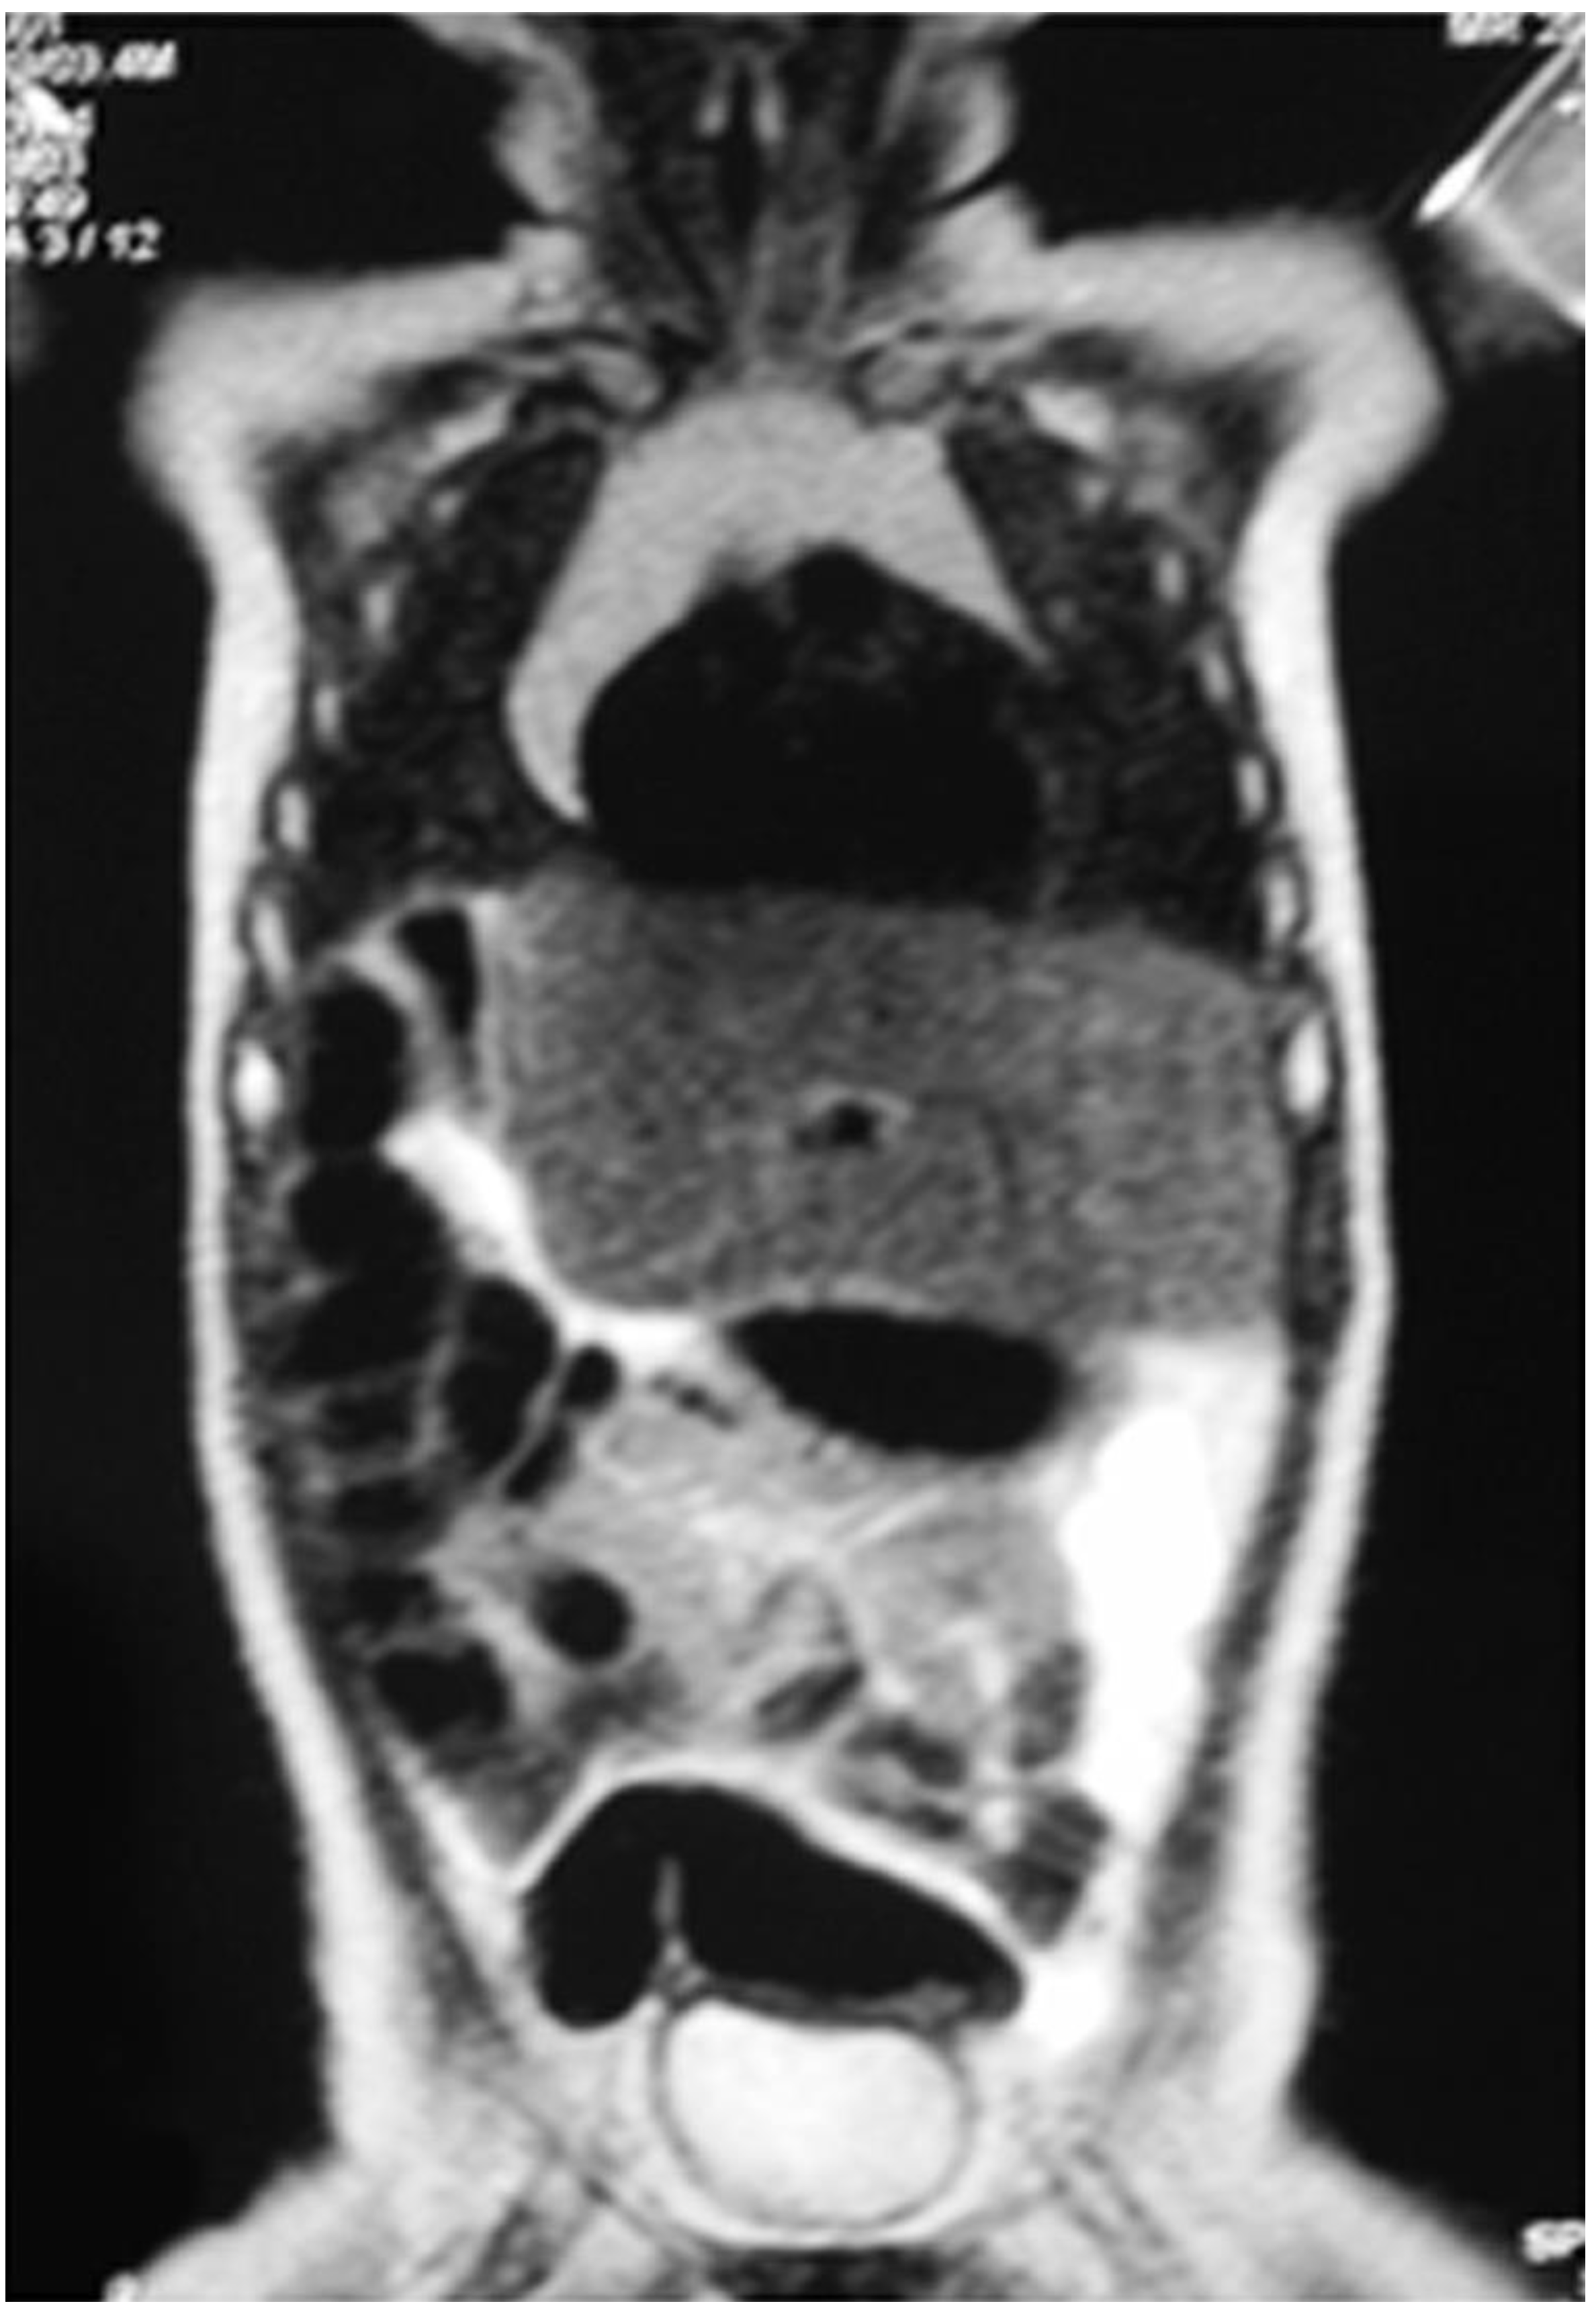

On the 7th postoperative day, the patient was discharged. The patient was completely asymptomatic and administered postoperative chemotherapy with two subsequent cycles of cisplatin. At 6 months follow-up, the total body MRI showed no recurrence of disease and hepatic compensatory hypertrophy of the left liver (Figure 2).

Figure 2. Total body MRI at 6 months follow-up showing no recurrence of disease.